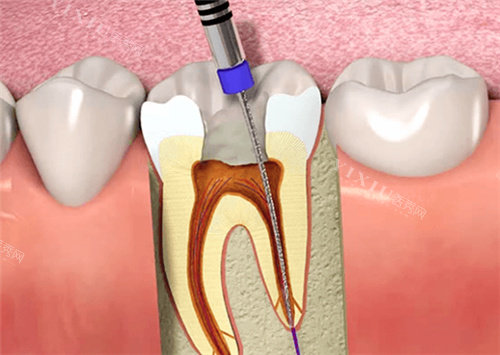

牙体治疗类

根管治疗(前牙):550元起

根管治疗(后牙):900元起

显微根管治疗:1500元起

牙髓失活术:200元起

根尖诱导成形术:500元起